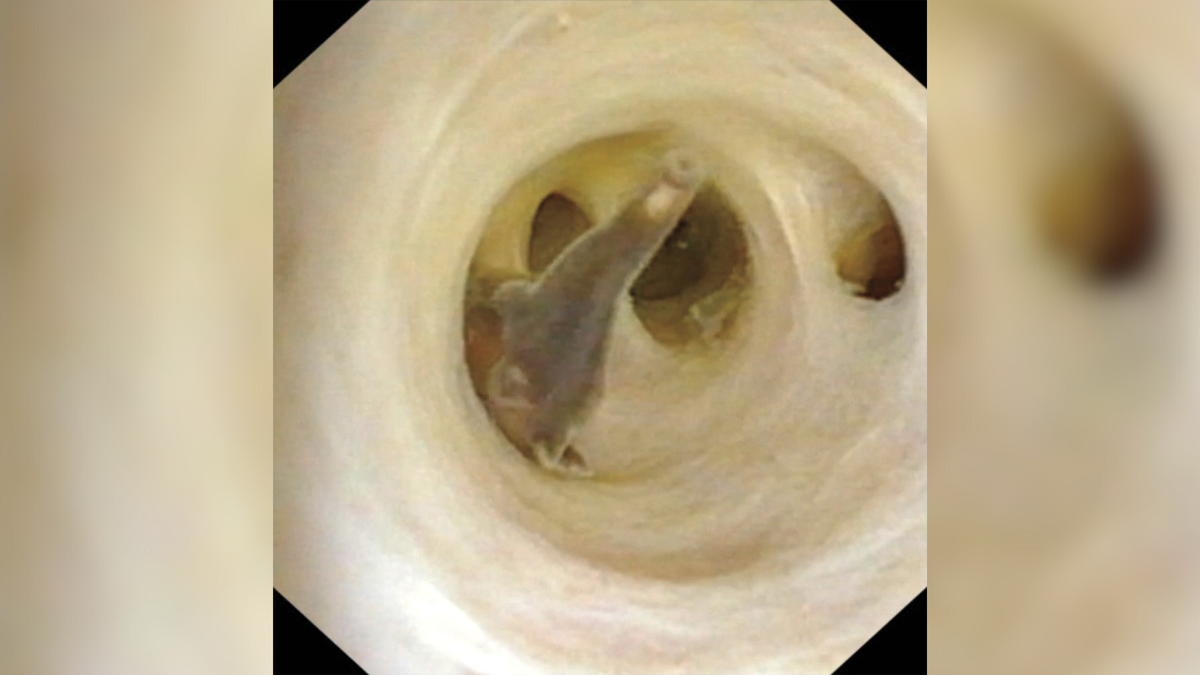

Midlands Colorectal